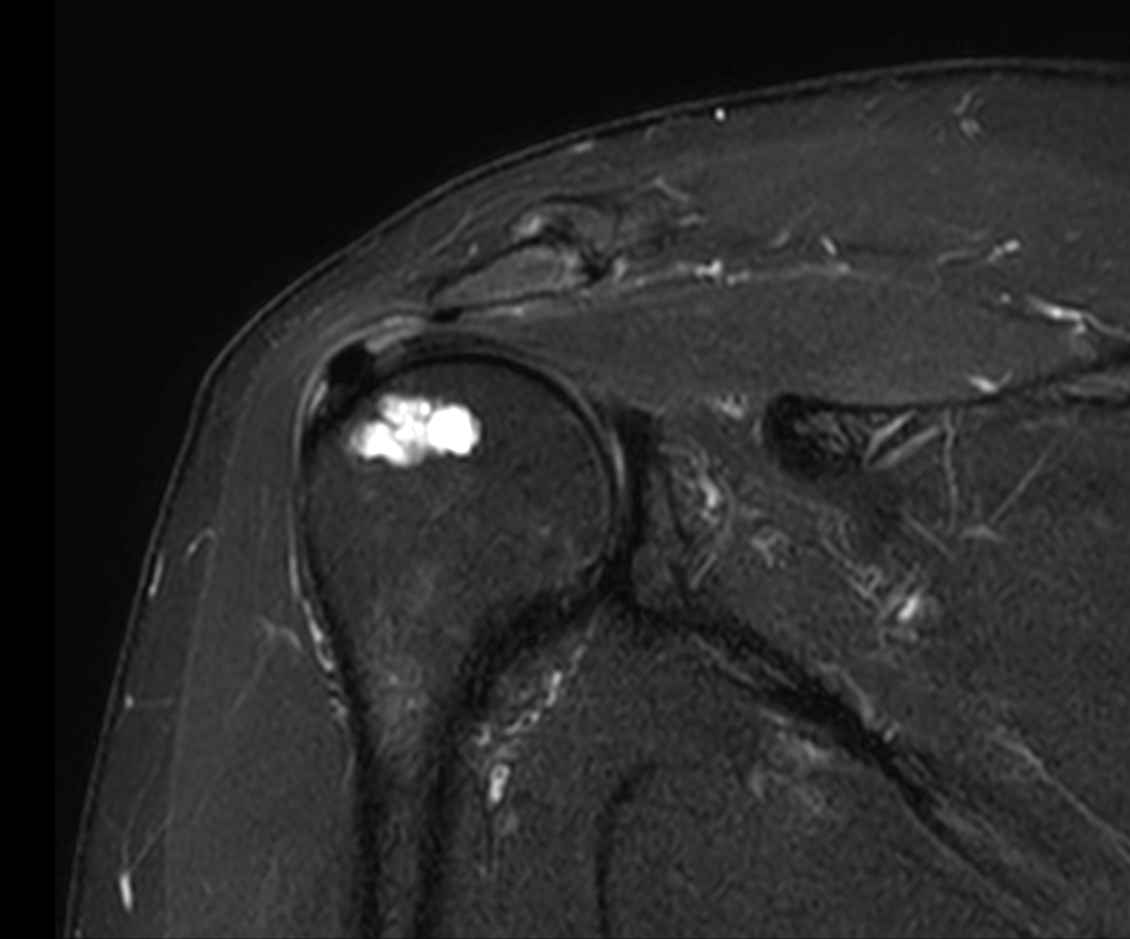

Coronal T1w SPIR